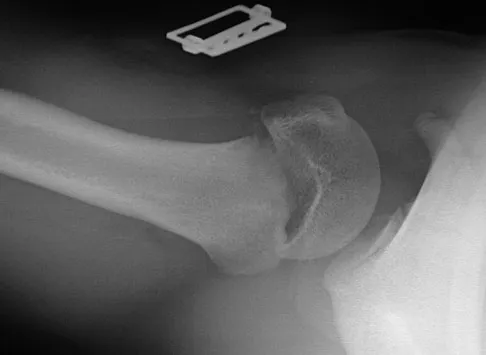

Figures 10a and 10b show the radiographs of a 47-year-old man who reports pain in both shoulders. He has a history of leukemia that was treated with chemotherapy and high-dose cortisone. What is the most reliable treatment option for pain relief in this patient?

Explanation

The radiographs reveal osteonecrosis with collapse. The most reliable and durable treatment for osteonecrosis of the humeral head remains prosthetic shoulder arthroplasty. Osteonecrosis of the humeral head may be seen after the use of steroids, and there is an increasing demand for shoulder arthroplasty in young people because of the use of high-dose steroids in chemotherapy regimes for the treatment of malignant tumors. The indications for most shoulder arthrodeses today include posttraumatic brachial plexus injury, paralytic disorders in infancy, insufficiency of the deltoid muscle and rotator cuff, chronic infection, failed revision arthroplasty, severe refractory instability, and bone deficiency following resection of a tumor in the proximal aspect of the humerus. Clearly, the role of arthroscopy and related minimally invasive techniques in the treatment of humeral head osteonecrosis remains unknown. Hasan SS, Romeo AA: Nontraumatic osteonecrosis of the humeral head. J Shoulder Elbow Surg 2002;11:281-298. Hattrup SJ: Indications, technique, and results of shoulder arthroplasty in osteonecrosis. Orthop Clin North Am 1998;29:445-451.